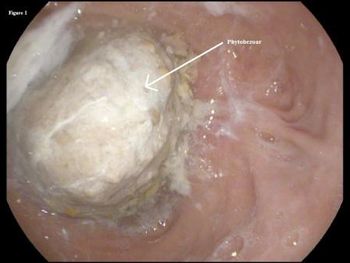

This 42-year-old woman lost 100 lb during the year after gastric bypass surgery. Now, she is diagnosed as having an ulcer. What might be the cause of the lesion?